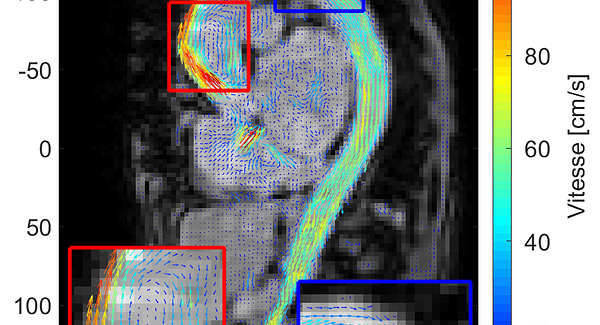

Visualiser le sang en mouvement : voyage au cœur de l’IRM de flux 4D

Une technologie encore méconnue qui pourrait transformer notre compréhension du système cardiovasculaire. Et si on pouvait filmer le sang en...